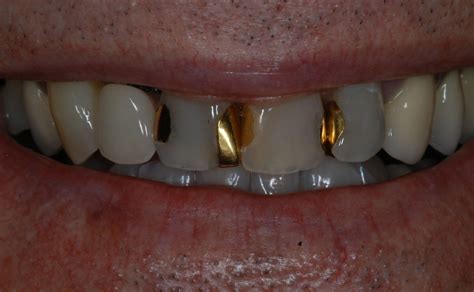

Types of Materials Used in Fillings

Modern dentistry offers several options for restorative materials, each with unique advantages regarding durability, aesthetics, and cost. Choosing the right material for your teeth and fillings often depends on the location of the cavity and your personal aesthetic preferences.

Material Type Key Characteristics Best For

Composite Resin Tooth-colored, blends naturally with existing teeth. Visible teeth, small to mid-sized cavities.

Amalgam (Silver) Highly durable and cost-effective. Back teeth (molars) where biting forces are high.

Ceramic (Porcelain) Resistant to staining and aesthetically superior. Patients desiring high-end cosmetic results.

Glass Ionomer Releases fluoride, helping prevent future decay. Children or root surfaces near the gumline.